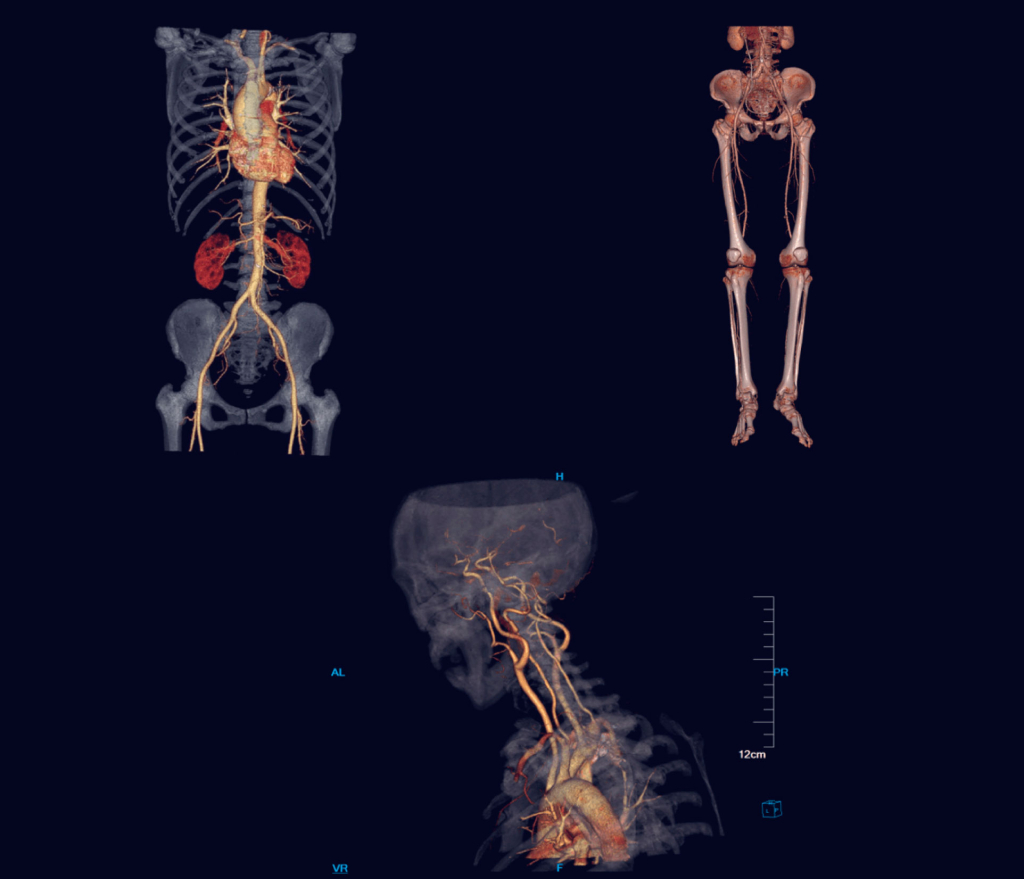

Визуализация Insitum 16-увидеть невидимое

Формирование скана и объемного изображения производится на цифровой матрице, которая состоит 1024 х 1024 элементов. Большое количество пикселей способствует формированию более контрастного, четкого и детального изображения всех анатомических областей с большим полем обзора.

Разрешение отображения схожих по контрасту объектов составляет 3 мм при 0.3%. Пространственное разрешение (отображение объектов с высокой контрастностью) равно 20 пара линий/см при отсечке. Это одни из лучших показателей в томографах это класса.

Программное обеспечение к компьютерному томографу Insitum 16 представляет собой целостную диагностическую платформу, которая сочетает рабочую станцию с графическими редакторами и специальными клиническими приложениями, интуитивных программ постобработки и передачи данных, пакет технологий для телемедицины. Компания SinoVision постоянно осуществляет обновление программного обеспечения и поддержку в онлайн режиме.

Основными особенностями рентгеновских сканеров SinoVision являются сниженная лучевая нагрузка, высокая скорость сканирования с четкими и детальными изображениями и выявление небольших патологических изменений во всех частях человеческого тела. Области применения - опорно-двигательный аппарат, структуры головного мозга, органы брюшной полости и малого таза, ангиографическое исследование крупных и периферических кровеносных сосудов.